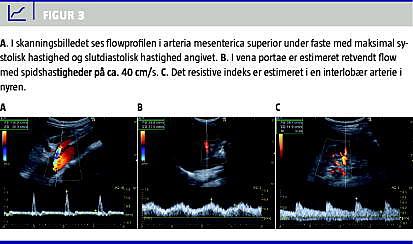

Arteria mesenterica superior

I faste har arteria mesenterica superior plug flow med en trifasisk profil, som ligner den i aorta abdominalis med hurtige op- og nedslag i systolen (Figur 3 ). Plug flow opstår, når blodet har omtrent samme hastighed, hvad enten det befinder sig i centrum eller mere perifert i karlumen. Spektralkurven er derfor skarpttegnet og overvejende uafhængig af range gate -bredde [4, 7]. Den trifasiske flowprofil skyldes, at der i tidlig diastole er et retrogradt flow og i sen diastole et antegradt flow. Efter fødeindtag sænkes modstanden i karret, og en øget maksimal systolisk hastighed (PSV) og slutdiastolisk hastighed (EDV) indtræder med udelukkende positivt flow i diastolen for at imødegå det øgede iltkrav fra tarmen. Flowprofilen ændres fra plug flow til laminart flow, der er kendetegnet ved faldende hastigheder i lumen fra centrum mod periferien, hvilket resulterer i en bredere spektralkurve [6, 8]. Ved betydende stenose i arteria mesenterica superior som ved kronisk intestinal iskæmi ses hos fastende patienter PSV > 275 cm/s, som øges yderligere postprandialt, samt EDV > 50 cm/s. Normalværdien ved faste er for PSV 130 (± 18) cm/s og EDV 24 (± 4) cm/s [7].

Vena portae

Flowet i vena portae estimeres med transduceren placeret interkostalt i patientens højre flanke. Herved opnås en brugbar insonationsvinkel, og overlejrende tarmluft undgås. Ved normalt flow i vena portae vil farve-Doppler inden for colour box vise antegradt (hepatopetalt) flow. Dvs. at flow i det portale system, der løber ind i leveren ved interkostal skannerposition, derfor bevæger sig mod transduceren. Range gate placeres i lumen og indstilles tilstrækkeligt smal, så signal fra arteria hepatica, der forløber i tæt relation hertil, undgås. Flowet er positivt og laminart med hastigheder på 20-40 cm/s. Der ses en diskret fasisk bevægelse i flowet synkront med hjertefrekvensen, hvilket skyldes tilbagetransmitterede trykændringer fra højre atrium via levervenerne, og en langsommere fluktuation, som skyldes respirationssynkrone trykændringer i thorax (Figur 3) [5].

RI er en ratio, dvs. uden benævnelse og følgelig vinkeluafhængig. RI, der beregnes ud fra spektrogrammet og ofte automatisk af skanneren, er et udtryk for karrets komplians og modstand. Normalværdien for RI er 0,60-0,70 [6, 9] (Figur 3).